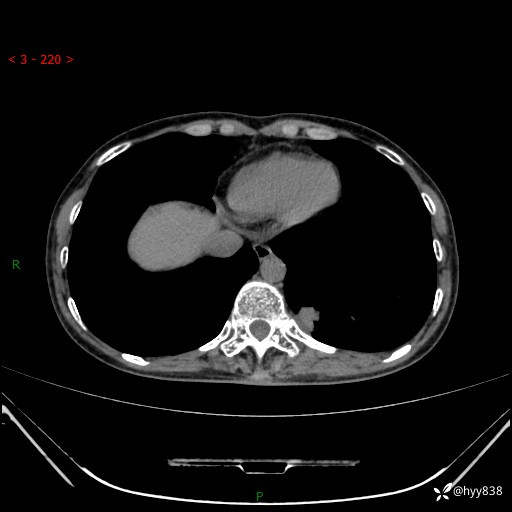

胸部CT平扫

增强动脉期+静脉期

各期CT值:48hu 65hu 76hu